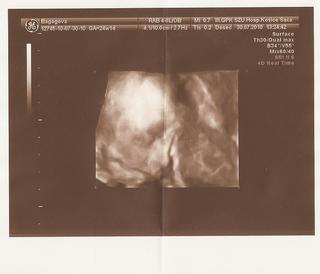

ahojte budúce mamičky, prajem všetkým pekný dník 🙂 ...my dnes ideme na 4D usg, veeeeľmi sa tešíme, konečne uvidíme svoju princeznú 🙂 ..ako sa dnes cítite, keď je tak horúco???